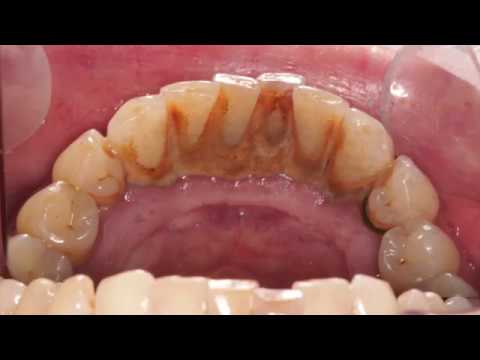

Before and After Scale and Polish - Dental Hygienist Telford - Dental Cleaning Before And After - See the incredible before and after of one of our new patients who had her first visit to a dental hygienist. On the first visit she had the plaque removed and on the ...

How Teeth Are Cleaned At The Dentist - Dental Cleaning Before And After - This video shows a close-up view of a routine dental cleaning by a dental hygienist. Watch how I use the ultrasonic to clean the teeth then polish after! If you like ...